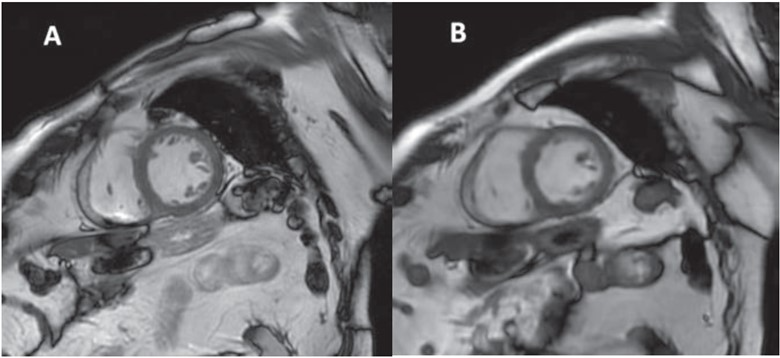

85-year-old patient with ischemic heart disease, who underwent cardiac MRI at 3 T.

A. Short-axis image from standard cine balanced SSFP breath-hold sequence.

B. Short-axis image from free-breathing accelerated cine sequence with deep-learning reconstruction. Images show normal appearance of left ventricular myocardium